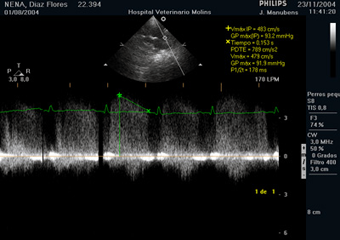

Figura 2. El Doppler espectral aplicado sobre el tracto de salida del ventrículo derecho muestra la presencia de un flujo de regurgitación diastólico de 4.83 m/s.